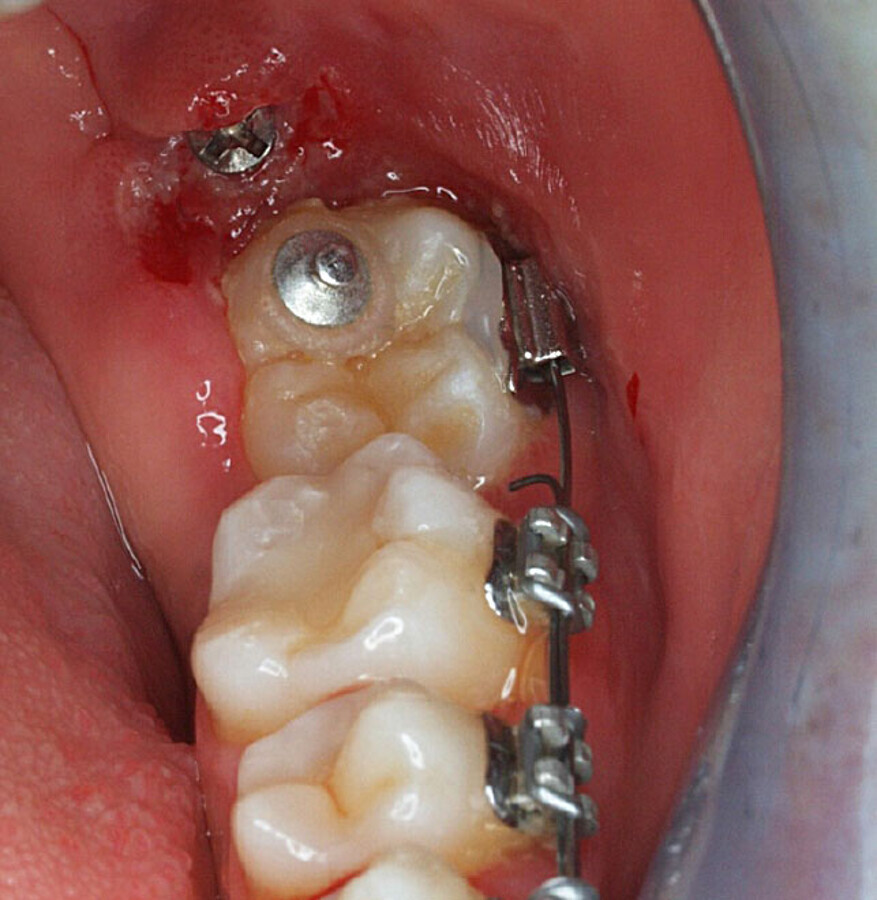

Aproximadamente 6 meses después, se prepara un anclaje esquelético con un tornillo de titanio autoperforante (D2.0 / L 12mm, Jeil Medical Corporation). Estos tornillos son más indicados para fijar injertos en bloque. Este anclaje permite enderezar el segundo molar por completo. En una primera fase, se tracciona desde el tornillo a un botón colocado en la cúspide distolingual del diente 37 con cadeneta elástica. Una vez el diente 37 está “desenclavado”, se termina de enderezar, cementando estratégicamente brackets y tubos de cementado directo y utilizando arcos elásticos NiTi.

Fotografía clínica de final de tracción.